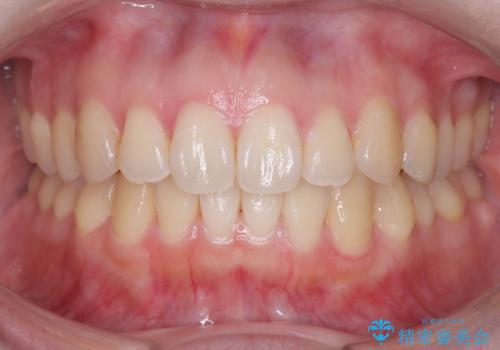

重度の不正咬合 Cl.Ⅱ div.2 を表のワイヤー矯正で綺麗に!

- 右下の第2小臼歯は完全に埋伏していたため、これは歯列に勘定せず計画をたてた

→右側は上顎第1小臼歯の抜歯によるCl.Ⅰ目標

→左側は上顎第1小臼歯抜歯・下顎第2小臼歯の抜歯によるCl.Ⅰ目標

一般的なCl.Ⅱ div.2の治療法に基づき、上顎のフレアアウト後に抜歯を行い、スペースクローズに移行した